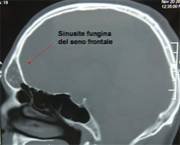

La TC mostra l’interessamento sia mucoso che osseo dei seni paranasali da parte dell’infezione micotica, in tal caso particolarmente aggressiva e con frequente estensione orbitaria ed endocranica (fossa cranica anteriore e media), con caratteristiche e patognomoniche calcificazioni endosinusali. La RMN è caratterizzata anche in questo caso dalla assenza di segnale e può contribuire, in tal senso alla diagnosi differenziale con le forme neoplastiche.